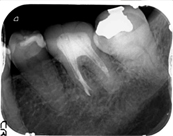

左下の奥歯に強い痛みを訴え来院。根管治療を施した。根管治療終了後、痛みはなくなり、炎症も認めないため、根管充填を施した。

左下の奥歯に強い痛みを訴え来院。根管治療を施した。根管治療終了後、痛みはなくなり、炎症も認めないため、根管充填を施した。